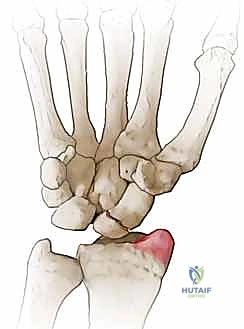

SNAC Wrist Stage I: The arthritic process is initially confined to the articulation between the distal pole of the scaphoid and the radial styloid. The proximal pole of the scaphoid, still attached to the lunate via the intact scapholunate interosseous ligament, maintains a relatively congruous, albeit altered, relationship with the scaphoid fossa of the radius. This is the ideal stage for distal pole excision.

Figure 3A: Arthritis localized between the distal pole of the scaphoid and the radial styloid (SNAC grade I).

The pathogenesis of the SNAC wrist is rooted in the uncoupling of the scaphoid's integrated biomechanical function. A scaphoid nonunion inevitably leads to the development of post-traumatic arthritis, primarily affecting the radioscaphoid joint. The progression timeline varies based on patient activity level and the specific morphology of the nonunion, but the vast majority of patients will demonstrate radiographic evidence of degenerative changes within 5 to 10 years post-injury. The fundamental cause is the abnormal, asynchronous motion between the ununited, frequently flexed distal scaphoid fragment and the articular surface of the radial styloid. This focal point of abnormal biomechanics leads to accelerated cartilage wear, subchondral sclerosis, and eventual joint space obliteration.

Distal pole excision is essentially an excisional arthroplasty. By removing the arthritic, impinging distal fragment, we eliminate the source of pain (the stylo-scaphoid impingement) and decompress the radioscaphoid joint. However, because the proximal fragment is left in situ, the SL ligament must be intact to prevent the remaining proximal scaphoid and lunate from collapsing into a severe, uncorrectable DISI deformity.